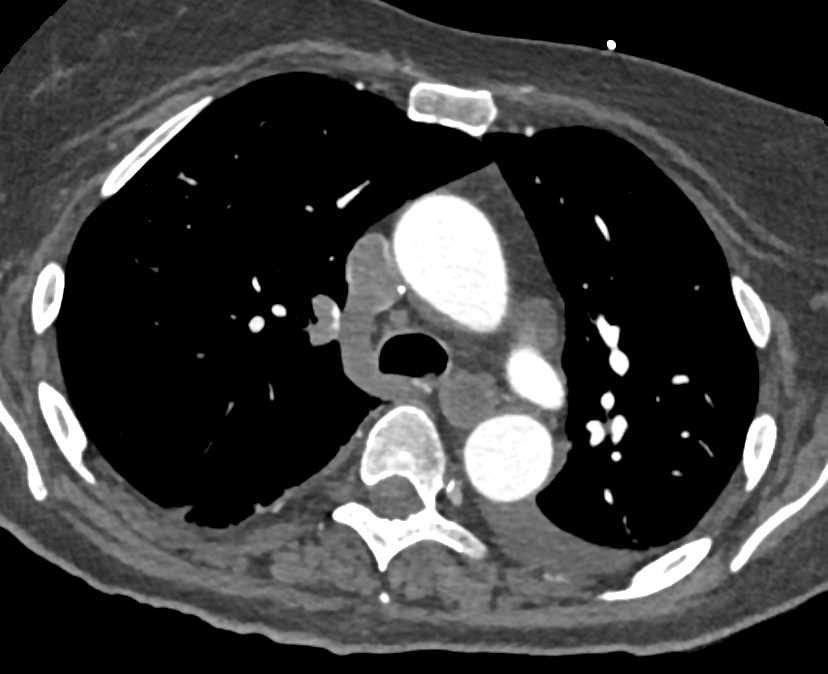

Pulmonary Embolism